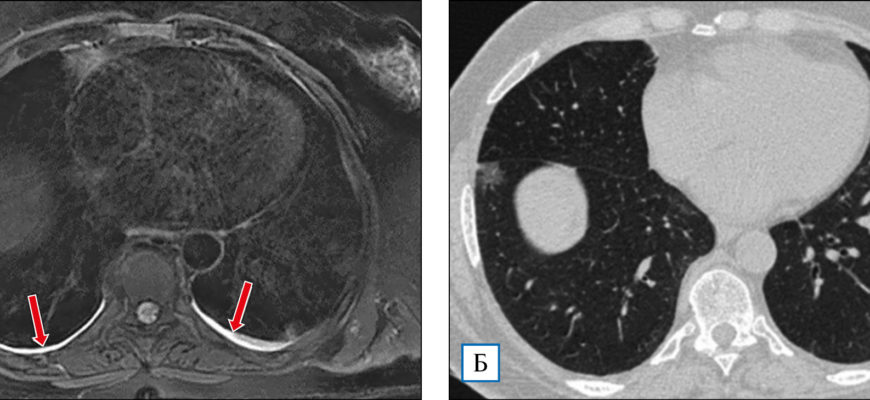

КТ и МРТ

Компьютерная томография (КТ) и магнитно-резонансная томография (МРТ) на сегодняшний день являются наиболее доступными методами диагностики различных заболеваний. Оба метода можно использовать для исследования легких при развитии пневмонии, но принцип их действия принципиально разный:

- Компьютерная томография (КТ) — более совершенная альтернатива рентгену. Компьютерная томография также использует рентгеновские лучи, но этот метод исследования намного эффективнее, он дает возможность досконально изучить структуру легких и бронхов. По этим причинам компьютерная томография используется в тех случаях, когда классический рентген не дал достаточных результатов.

- МРТ или магнитно-резонансная томография — принцип работы этого вида обследования основан на использовании магнитного поля, создаваемого действием огромного магнита. Томограф отображает трехмерное изображение органа, что позволяет детально изучить состояние последнего, а также степень воспаления в легких и многое другое.